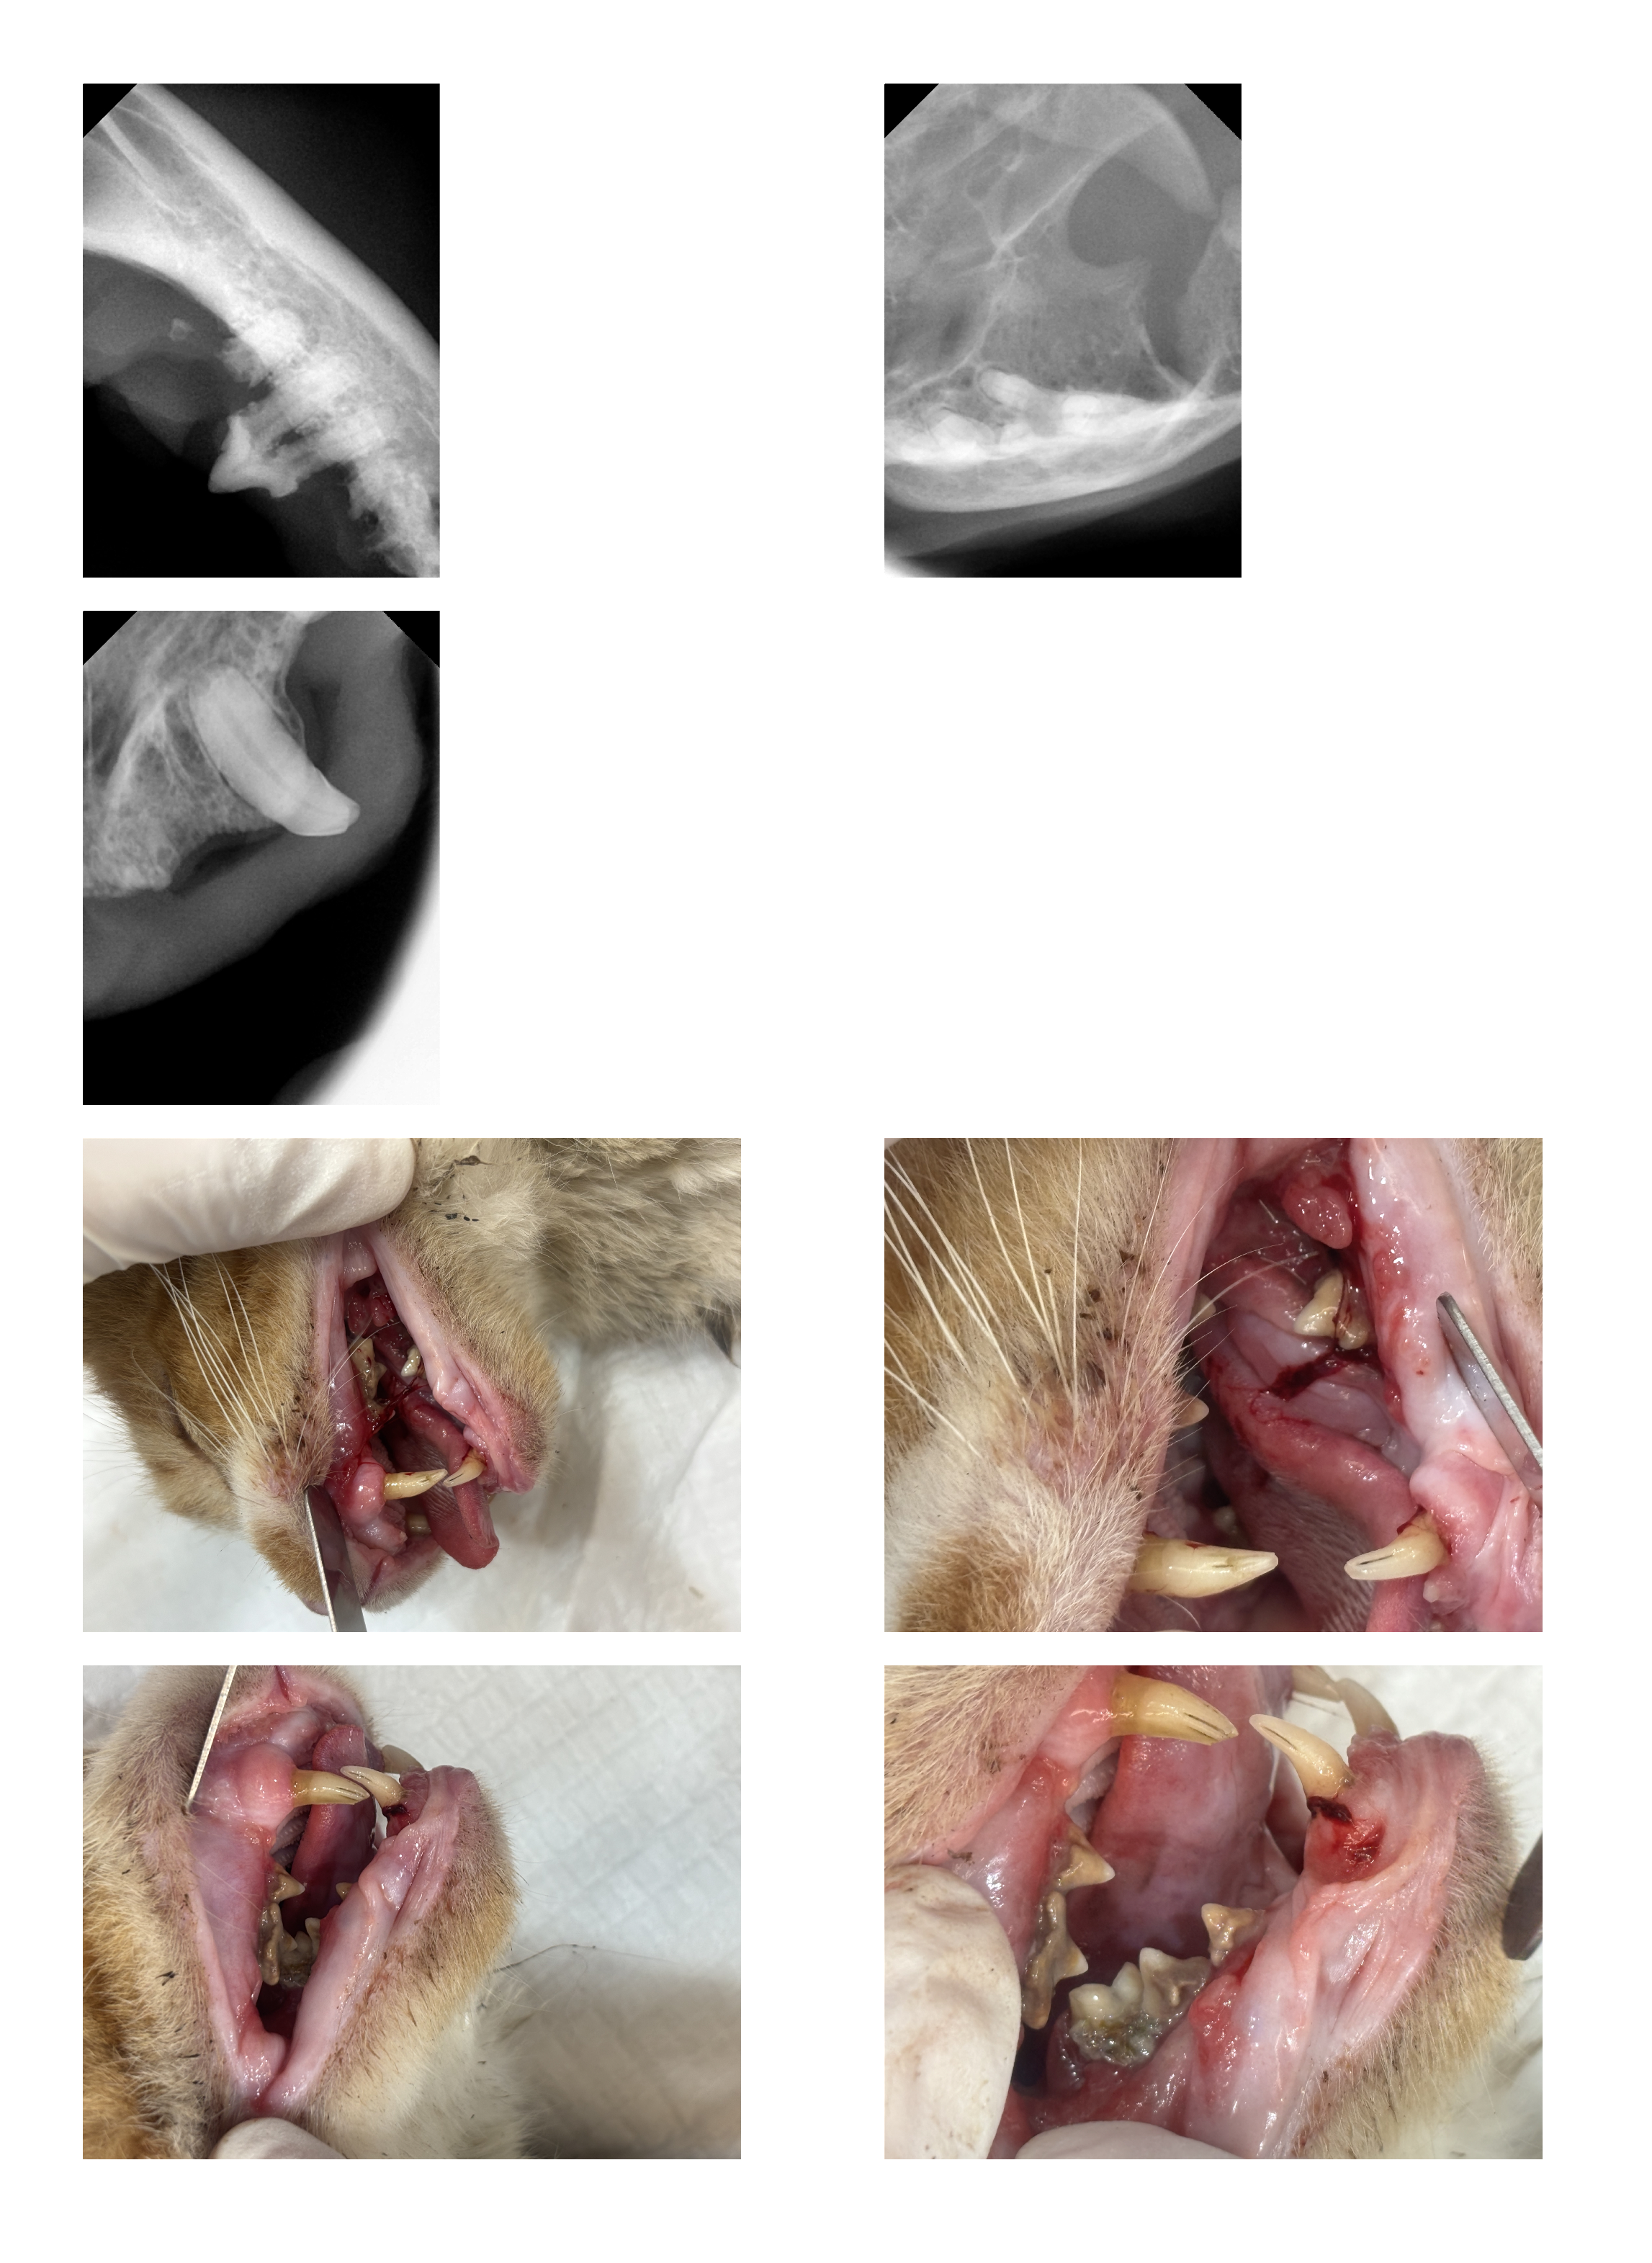

| 치료과정 | 호빵이는 저녁에도 습식을 먹으러 매일 나오지는 않던 녀석이라 구조가 걱정이었습니다. 습식 시간에 나타나길 기다리다가 한 차례 구조에 실패해 마음을 졸이게 했지만, 겨울집이나 여름집을 마련해 두는 곳에는 잘 머무르곤 했기에 이튿날인 10월 21일(화) 낮에 급식소와 집을 마련해 둔 곳 근처에 포획틀을 설치했고 무사히 구조할 수 있었습니다. 미리 연락해 둔 병원으로 곧바로 이동하였고, 사납고 사람 손을 타지 않는 성격인 터라 마취한 후 대기 시간을 가진 후 본격적인 검사에 들어갔습니다. 이 병원에서는 마취 후 상태를 보고 발치가 필요한지 아닌지를 판단한다고 하였는데요, 호빵이는 오랫동안 구내염을 앓아 왔기에 전발치가 필요한 상태임을 진단받았습니다. 그렇게 당일 모든 이빨에 대한 전발치를 진행하였고, 특히 목 안쪽에 염증이 심했던 상태라 조금 편하게 호흡을 할 수 있도록 추가적인 처치를 해 주셨다고 했습니다. 또 2주 동안 효과가 지속되는 항생제 처치도 진행하였습니다. 불행 중 다행히도 혈액 검사 결과 별다른 문제는 더 발견되지 않았습니다. 병원 방침상 발치 후 당일 퇴원한다고 하였으나, 힘든 수술을 한 아이를 바로 방사할 수는 없어 하루 동안 입원을 부탁드렸고 다음 날인 10월 22일(수) 오전에 호빵이를 데려와 원래 지내던 곳에 제자리 방사하였습니다. |

| 대상묘 치료중 사진 | ![]() ![]() ![]() ![]() |

[치료 중 사진]